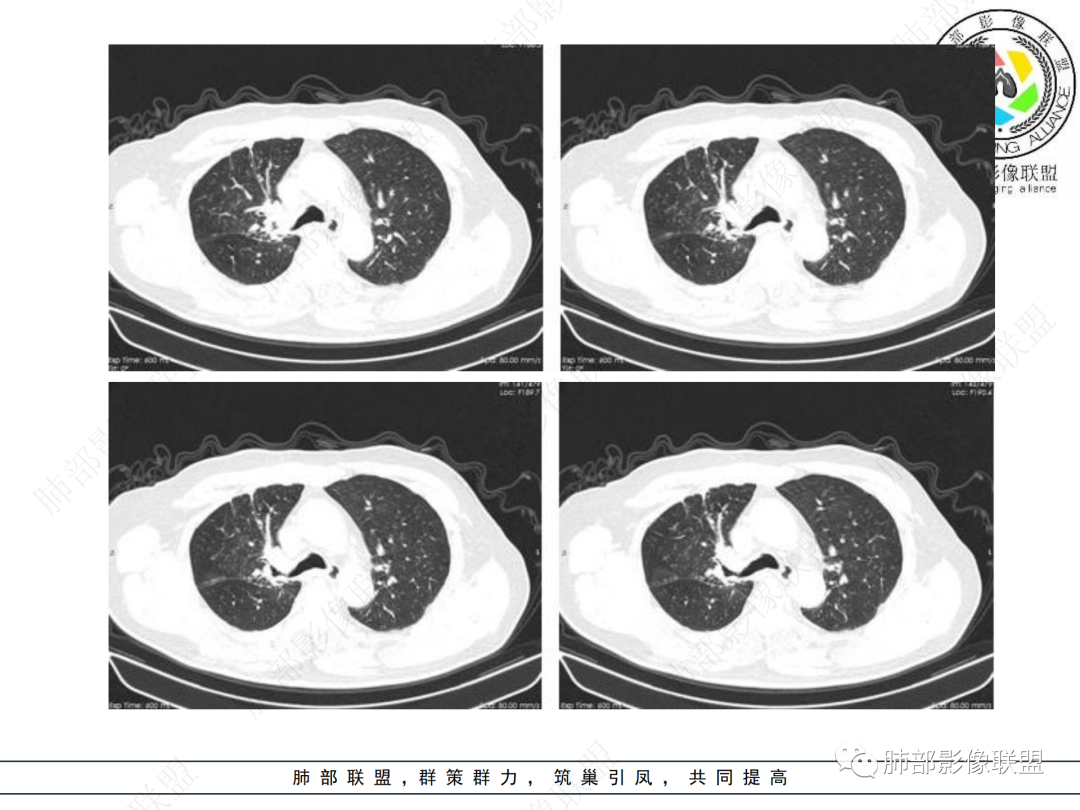

右肺上叶可见一团块影,边界清,有膨隆有凹陷,边缘可见毛刺,斜裂可见牵拉,不均匀强化,内可见液化,临近支气管未见明确阻塞,考虑腺癌可能,鉴别脓肿,结核等

右肺上叶团块,边缘毛糙,长索条,周围斑点影,邻近胸膜增厚,不均匀强化,其内小低密度灶边界清,考虑炎性肉芽肿,腺癌待排

老年男性,慢性病程,右肺上叶团块影,边界清晰,边缘毛刺,脐凹征,胸膜牵拉,不均匀强化,支气管壁增厚,考虑恶性,腺癌可能,鉴别肉芽肿、结核

右肺上叶见不规则团块,边缘清晰,周围可见长索条及斑片影,胸膜顶增厚,右侧斜裂部分增厚,右上肺体积略缩小,增强后不均匀强化,考虑炎性肉芽肿性病变,结核?鉴别腺癌

右侧胸廓变小,右肺上叶团块,边缘毛糙,长索条,周围斑点影,邻近胸膜增厚,气管不规整,密度不均,不均匀强化,考虑炎性肉芽肿,腺癌待排。

结合本病例,老年男性患者,慢性病程,急性加重,无吸烟史,影像学表现为右肺上叶尖后段斑片实变密度影,整体边界清晰,边缘平直收缩为主,周边散在纤维条索影,内部见支气管内粘液栓,血管影走形正常,没有明显破坏,增强扫描明显强化,缺乏典型分叶毛刺、胸膜改变,病灶也未显示清楚的磨玻璃勾边,病灶大而肺门纵隔未见肿大淋巴结,综合考虑慢性炎性肉芽肿可能性大。但恶性,结核能完全排除吗?我想对临床医生来说还是有很大考验的。